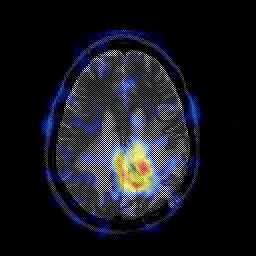

Glioblastoma multiforme overlay -- Slice #35

[Home][Help][Clinical][Tour 1][Tour 2][Tour 3] Slice 35